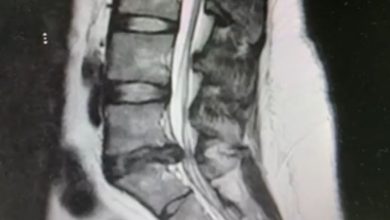

نجاح عملية جراحية باستخدام المنظار لإزالة غضروف ضاغط على الأعصاب في مجمع الملك عبدالله الطبي بجدة

نجح مجمع الملك عبدالله الطبي بجدة عضو تجمّع جدة الصحي الثاني في علاج حالة امرأة ثلاثينية كانت تعاني من آلام…